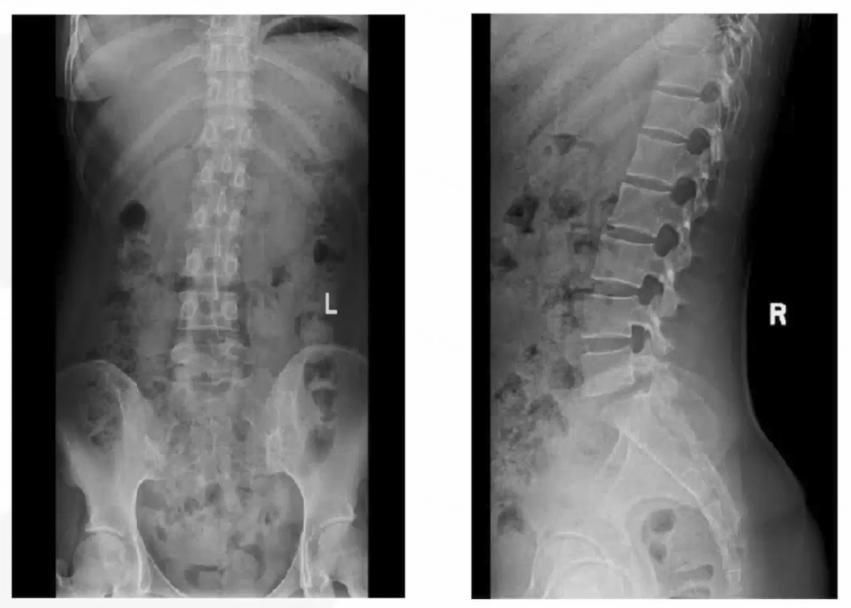

图1 患者X线正侧位图

图2 患者骶髂关节CT胸部CT:双肺陈旧病变,脾大;

骶髂关节CT:符合AS改变,建议结合临床;

腰椎X线:未见异常;

确实,如前文所见,患者的诊断十分清晰:青年女性,病史10年,近期加重,临床表现为多关节疼痛,累及中轴及外周关节,呈炎性腰背痛特点,检查HLA-B27阳性,骶髂关节X线、CT提示骶髂关节炎改变,根据1984年修订的纽约标准,可诊断为AS。